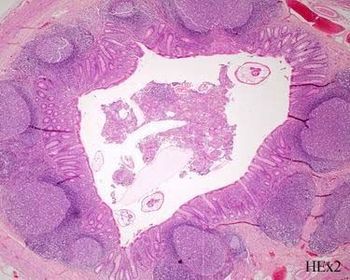

TISSUE TYPE: gland and stroma... specific glands of prostate PATHOLOGY: hyperplasia of gland and stroma DIAGNOSIS: benign prostatic hyperplasia KEY: U CAN SEE CORPORA AMYLECIA

TISSUE TYPE: u can see transitional epith. (not clear here) ... urinary bladder PATHOLOGY: black arrow: cystitis cystica red arrow: Brunn's nest of course u will see ova (not clear here) DIAGNOSIS: blihariziasis KEY: OVA N.B: differentaite between bladder and ureter Bilhariziasis .. just ureter will be complete circle ..(with same epith. changes) .. in intestine u can see ova or even the worm itself and no epith. changes .. squamous metaplasia can also be seen